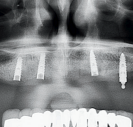

מטופל בן 84 הופנה למרפאה עם תותבת עליונה שנאחזה עד כה באמצעות ארבעה שתלים עם לוקטורים.

הבעיה

אחד השתלים כשל ונעקר. שלושה לוקטורים אינם מספיקים כדי לאחוז בתותבת שלמה בלסת העליונה. המטופל אינו מעוניין בשתלים נוספים.